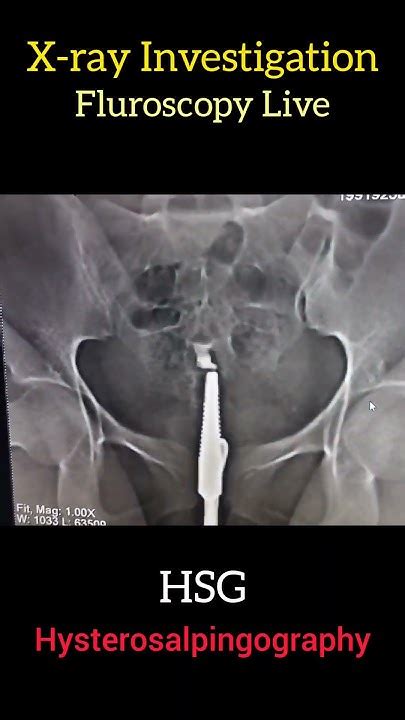

So, guys, what is an HSG X-ray ? At its core, an HSG X-ray, or hysterosalpingogram, is a special kind of imaging test that doctors use to get a good look at your uterus and fallopian tubes. Think of it as a sophisticated way to check if everything’s in the right place and functioning as it should in your reproductive system. The ‘HSG’ part stands for Hystero (uterus), Salpingo (fallopian tubes), and Gram (writing or recording), so it literally means a ‘writing of the uterus and tubes.’ This test is particularly crucial when a couple is experiencing difficulty getting pregnant, as it can help pinpoint specific issues that might be hindering conception. The procedure involves using a type of contrast dye and X-rays to create detailed images. The dye is introduced into the uterus through the cervix, and as it fills the uterine cavity and travels through the fallopian tubes, the X-rays capture its path. This allows your doctor to see the shape and size of your uterus, check if the fallopian tubes are open (patent), and identify any blockages, abnormalities, or scar tissue that could be causing problems. It’s a really valuable diagnostic tool because it gives a direct visual of these internal structures, which other tests might not be able to provide as clearly. We’ll get into the nitty-gritty of how it’s performed and why it’s such a big deal in just a moment, but for now, just remember it’s all about visualizing your uterus and fallopian tubes to understand reproductive health better.

Alright, let’s talk about the actual procedure, guys. Knowing what to expect can really ease any anxiety you might have about undergoing an HSG X-ray . First off, it’s important to know that the best time to schedule your HSG is usually shortly after your period ends but before ovulation occurs . This is because you definitely don’t want to be pregnant when you have this test done, and this timing ensures that. You’ll likely be asked to take some over-the-counter pain relief, like ibuprofen, about an hour before the procedure to help minimize any cramping. When you arrive at the clinic or hospital, you’ll change into a gown. The procedure itself is typically done by a radiologist or a gynecologist, often in a radiology suite. You’ll lie on an examination table, similar to how you would for a Pap smear. The doctor will then insert a speculum into your vagina to visualize the cervix, just like during a Pap test. Next, a thin catheter is gently inserted through the cervix into the uterus. This might feel a bit uncomfortable or cause some mild cramping. Once the catheter is in place, the contrast dye will be slowly injected through it. As the dye fills your uterus and flows into the fallopian tubes, the radiologist will take a series of X-ray images. You might feel some pressure or more cramping as the dye is injected. Some women describe it as feeling like menstrual cramps, while others find it more intense. It’s usually over fairly quickly, typically taking about 15-30 minutes from start to finish. After the X-rays are taken, the catheter is removed. You’ll then be able to get up and go about your day, though you might experience some mild cramping or spotting afterward. It’s really not as bad as it sounds, and the information it provides is invaluable!